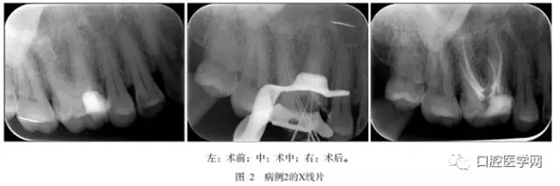

病例2,患者男,37歲,2013年11月因右上后牙食物嵌塞到青島市口腔醫(yī)院牙體牙髓科就診?;颊?年前曾于外院行銀汞合金齲齒充填術(shù),現(xiàn)部分充填體脫落。檢查:右側(cè)上頜第一磨牙面及近中處銀汞充填體松動(dòng)和部分脫落,探診無疼痛,叩診無疼痛,冷診疼痛,持續(xù)數(shù)十秒。X線片示:右上第一磨牙面及近中面舊充填體高密度影像已經(jīng)有部分與髓角相連,根尖區(qū)未見明顯低密度影像,腭側(cè)根根管影像模糊不清,似與二頰根對稱分布(圖2左)。

待無癥狀和根管無滲出后,Mtwo機(jī)用鎳鈦器械(VDW公司,德國)預(yù)備根管,25號0.6錐度主尖示尖(圖1中,圖2中),熱凝牙膠(KaVo公司,美國)行根管充填術(shù)。術(shù)后X線片示患牙根充恰填(圖1右,圖2右)。術(shù)后3個(gè)月復(fù)查,患者無任何不適,X線片顯示根尖區(qū)未有病變發(fā)生,治療效果佳。